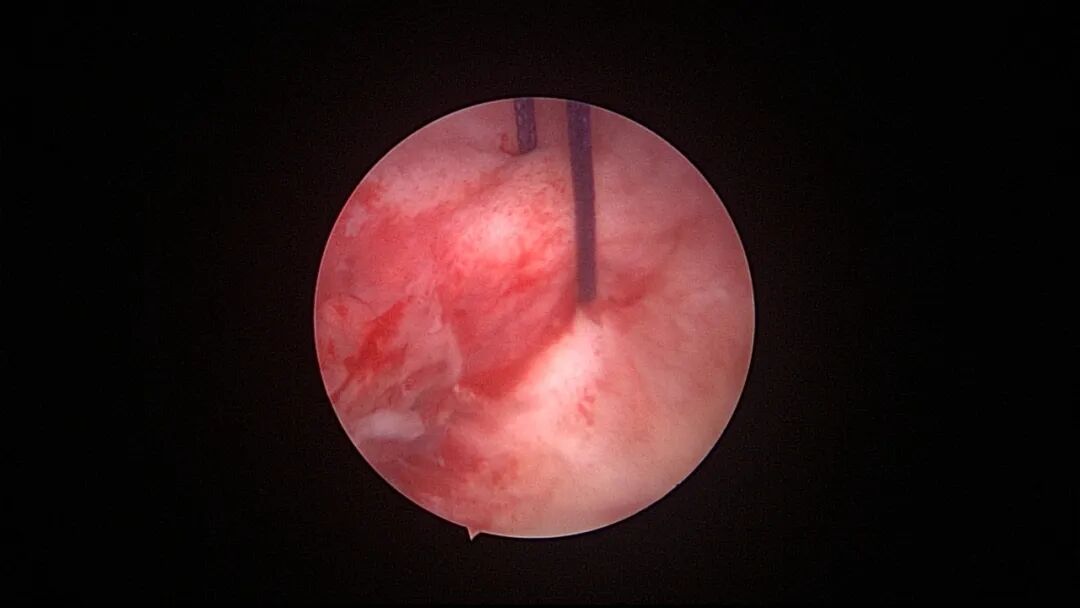

外院取环失败,子宫穿孔,盆腔积血

为了宫腔镜手术平稳顺利进行,宫腔镜术前准备及安全评估非常重要,尤其是充分的安全评估能有效减少并发症的发生。阴道情况:萎缩、纵膈、斜膈等可能导致扩阴器置入困难。肥胖病人、高个子病人阴道很深,宫颈可能难以暴露;宫颈情况:绝经后病人宫颈萎缩、狭窄、坚硬,加之穹隆展平,宫颈难以夹持、难以扩张;宫颈管弯曲、宫颈肌瘤、巨大息肉、粘膜皱襞隐窝、巨大纳囊等,可能阻挡宫腔镜进入宫腔;子宫情况:子宫萎缩,宫腔狭小,子宫极度前屈、后屈、侧屈等极端位置常常导致宫腔镜置入困难;既往盆腔手术史:子宫与盆腔器官粘连可能导致子宫极端位置,或者宫深超出预期。近期手术情况:外院取环失败、人流不全、宫腔探查或试图分粘中途放弃等病人,子宫可能存在假道、穿孔或盆腔积血等损伤。这类病人评估重点:前次手术医院级别、既往分娩情况、安环多少年、月经情况、闭经或绝经时间、手术日期、手术时间长短、是否麻醉、术后有无腹痛、有无阴道出血、B超情况、腹部平片、血糖血压等。宫腔镜术前需再次复查B超,手术医生到B超室了解子宫位置、大小、有无损伤、节育环种类及位置、是否嵌顿、盆腔有无积液等细节。